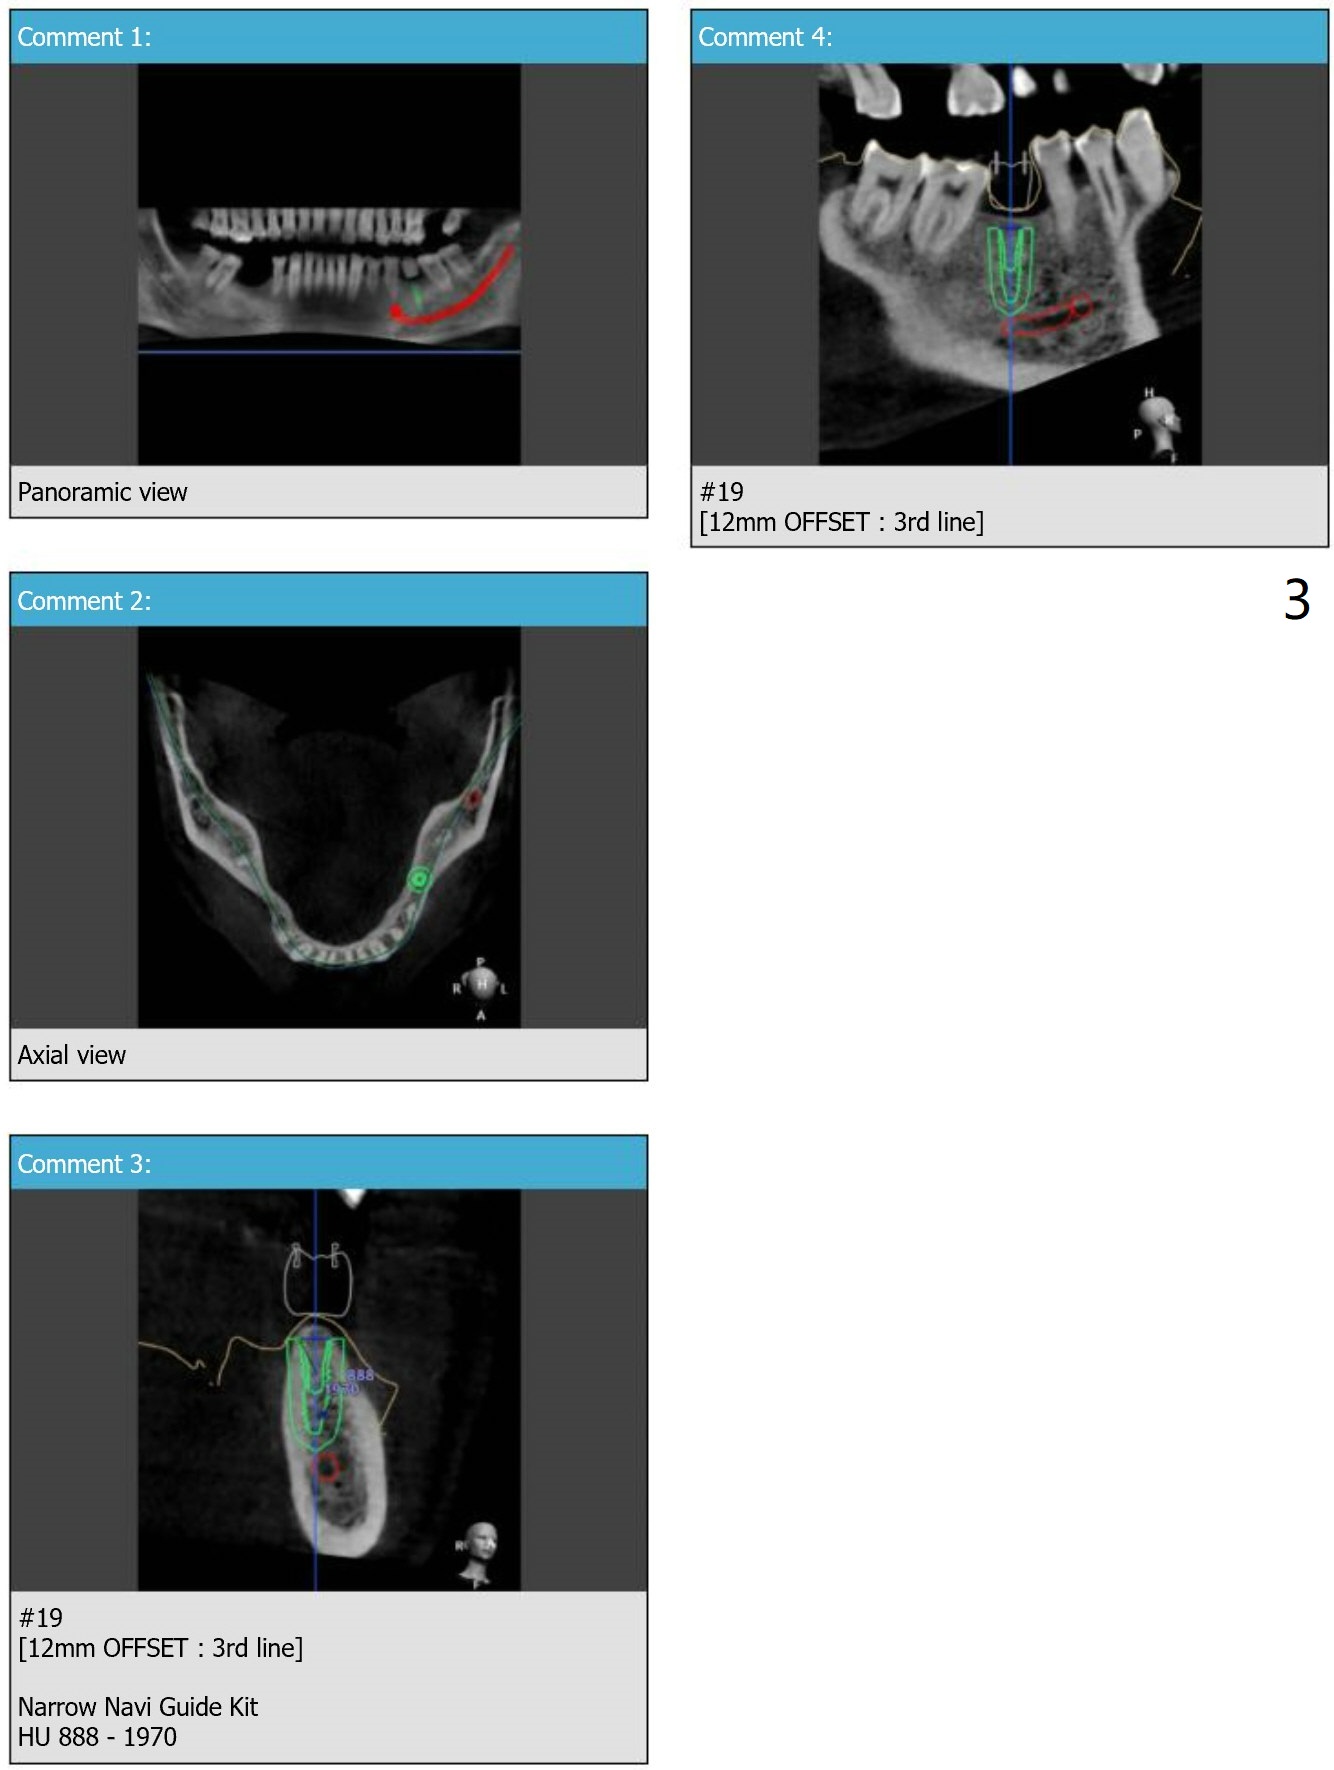

After cementation of an implant crown at #15, a 62-year-old man requests an implant at #19 to replace a RPD. Instead of 1-piece implant, a 2-piece one is chosen (Fig.1-3).